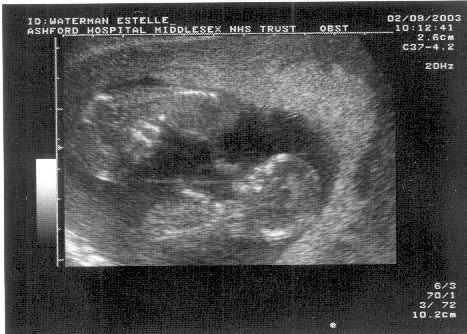

Yup, on 2nd september, Estelle

and Nick went to Ashford Hospital

for their 12 week scan,

expecting to later surprise everyone at work by bringing in an

ultrasound and announcing that we were going to be parents

again.

We weren't expecting quite such a surprise ourselves! TWINS!

Pics:

Another baby: